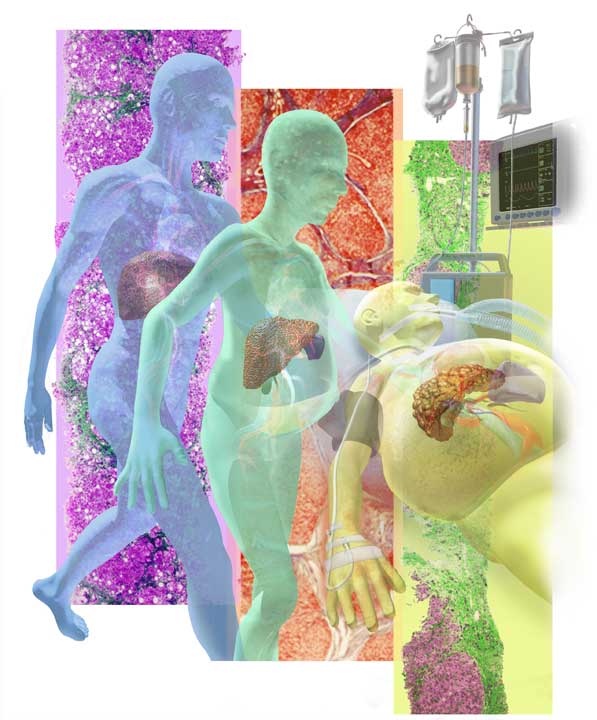

Collage for Nursing 2002, Magazine

Interpretation on the causes of respiratory infections and pneumonia